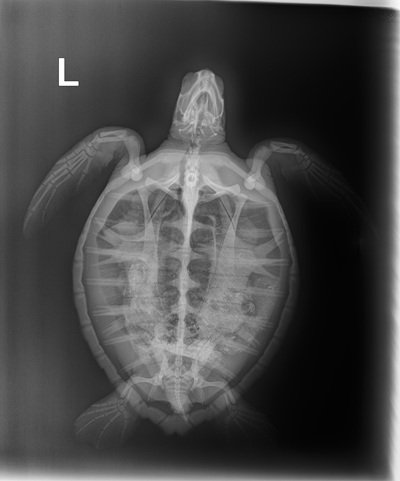

Date Stranded: March 22, 2026

Reason for Stranding

Stuck in the Boca Chica Jetties

Patient History

1.7 kg Atlantic Green

Patient Injuries

Plastron: a few urchin spines

Patient Treatments

In House Bloods:PCV: 33 %, TS: 3.6 , Glucose: 87, Meds administered: Standard protocol (Ceftaz, VitB & Normosol)